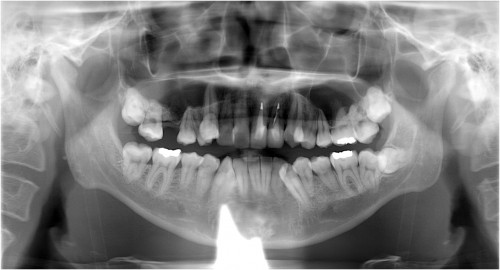

歯周病の進行度

歯ぐきの下の状態

左から

歯肉炎:歯周病の一歩手前の状態で歯ぐきに炎症が起きている状態で

す。

軽度歯周炎:歯周炎ポケットが4~5mmの状態です。

中度歯周炎:歯周ポケットが6~7mmの状態です。

重度歯周炎:歯周ポケットが7mm以上の状態です。

歯ぐきの状態